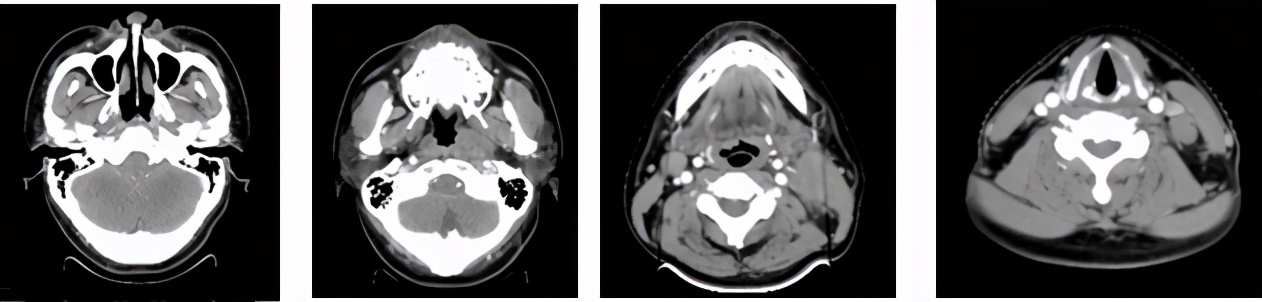

治疗前CT(2015.1)

治疗后随访磁共振(2015.9)鼻咽部及颈部均达CR